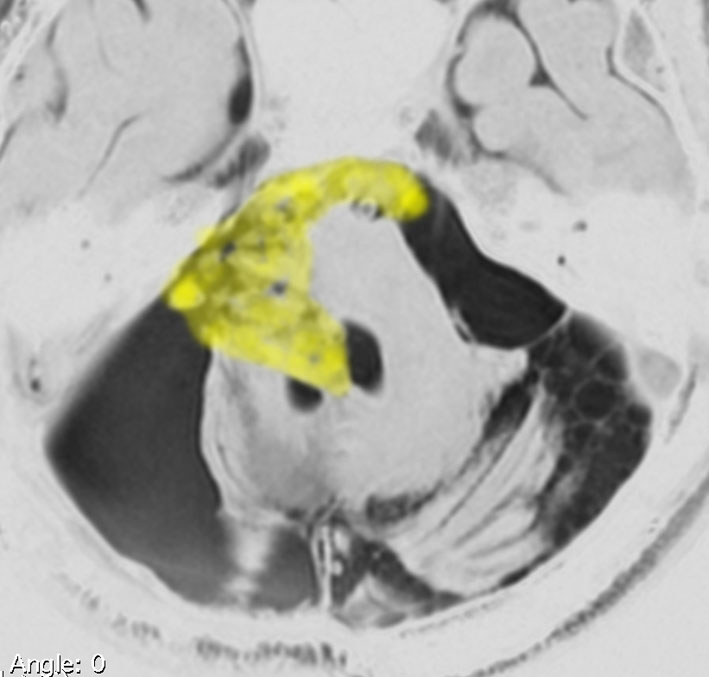

なぜ脳幹部からの無理な剥離が必要な手術を勧めるか

30歳くらいの時に初回の開頭手術で部分摘出を受けて,現在70代の患者さんの画像です。黄色は今も残っている腫瘍です。2度目の開頭手術,3度目の開頭手術では癒着で脳幹部や脳神経からの剥離が全くできませんでした。現在でも脳幹部に入り込むように腫瘍がゆっくり大きくなっていて,体幹失調のために車椅子生活です。顔面神経麻痺,嚥下障害,構語障害,眼球運動障害などもあります。髄液吸収障害による水頭症を併発してシャント手術も受けています。

この患者さんの40年の経過はいろいろなことを教えてくれます。似たような患者さんをたくさん見てくると,初回手術で取りきれなかった類表皮のう胞を,2度目の開頭手術で完全摘出することはとても難しいという経験を積みます。

数十年後のことを考えるのであれば,初回手術で完全摘出するべきです